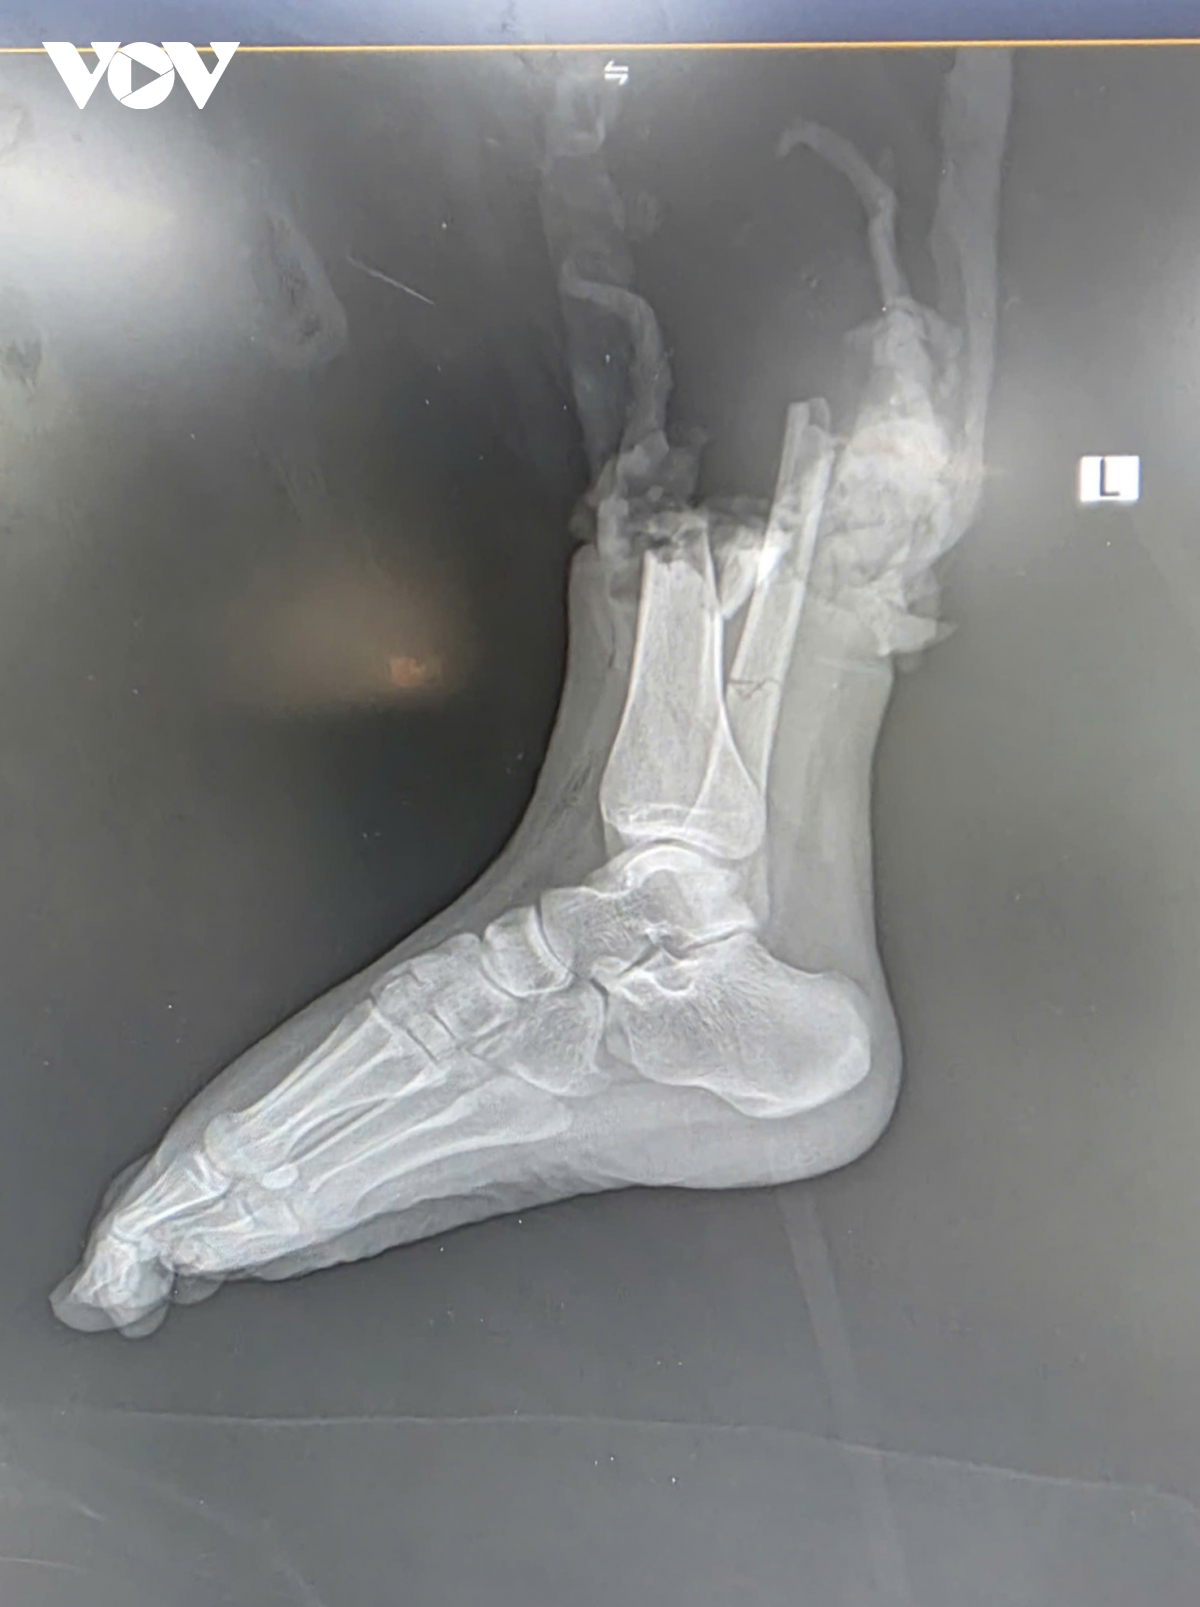

Thời điểm xảy ra vụ việc, một người đàn ông điều khiển mô tô phân khối lớn di chuyển với tốc độ cao đã va chạm mạnh với xe máy Honda Wave Alpha chở hai người. Cú đâm khiến hai người trên xe máy bị thương nặng, trong đó chị Đ.P (19 tuổi, quê Bắc Ninh), người điều khiển xe máy bị đứt lìa ở ví trí phức tạp, 1/3 dưới cẳng chân phải, kèm dập nát phần mềm.

Ngay sau tai nạn, chị Đ.P được sơ cứu và nhanh chóng chuyển tới Bệnh viện Trung ương Quân đội 108 trong “thời gian vàng” – khoảng 2 giờ sau chấn thương. Trong đêm khuya, kíp y bác sĩ đã nhanh chóng tiến hành cắt lọc, xử lý tổn thương, nối mạch máu, thần kinh, gân cơ và xương. Sau hơn 6 giờ phẫu thuật căng thẳng, phần chi thể đứt rời được trồng nối thành công. Sau phẫu thuật gần 2 tuần, bệnh nhân đã khỏe mạnh và có thể cử động được các ngón chân, cho thấy kết quả phục hồi khả quan.